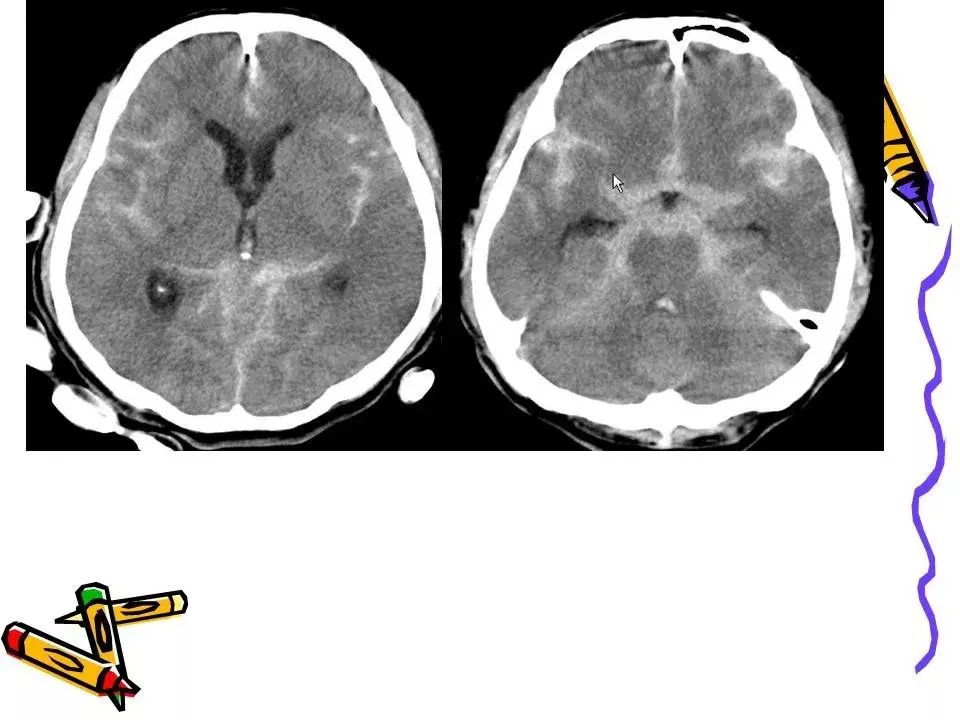

>常见颅脑外伤CT诊断(PPT)

常见颅脑外伤CT诊断(PPT)